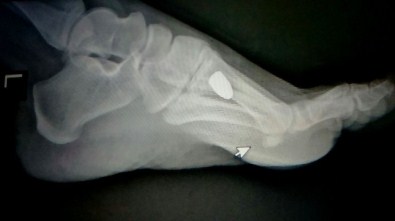

Acil serviste tedavi altına alınan Akbay’ın çekilen filminde ayağına saplanan bir mermi olduğu görüldü.

Olay sonrası hayati tehlikesi bulunmayan Akbay ayağındaki mermi çekirdeğinin çıkarılması için ameliyathaneye alınırken, olayla ilgili araştırma sürüyor.